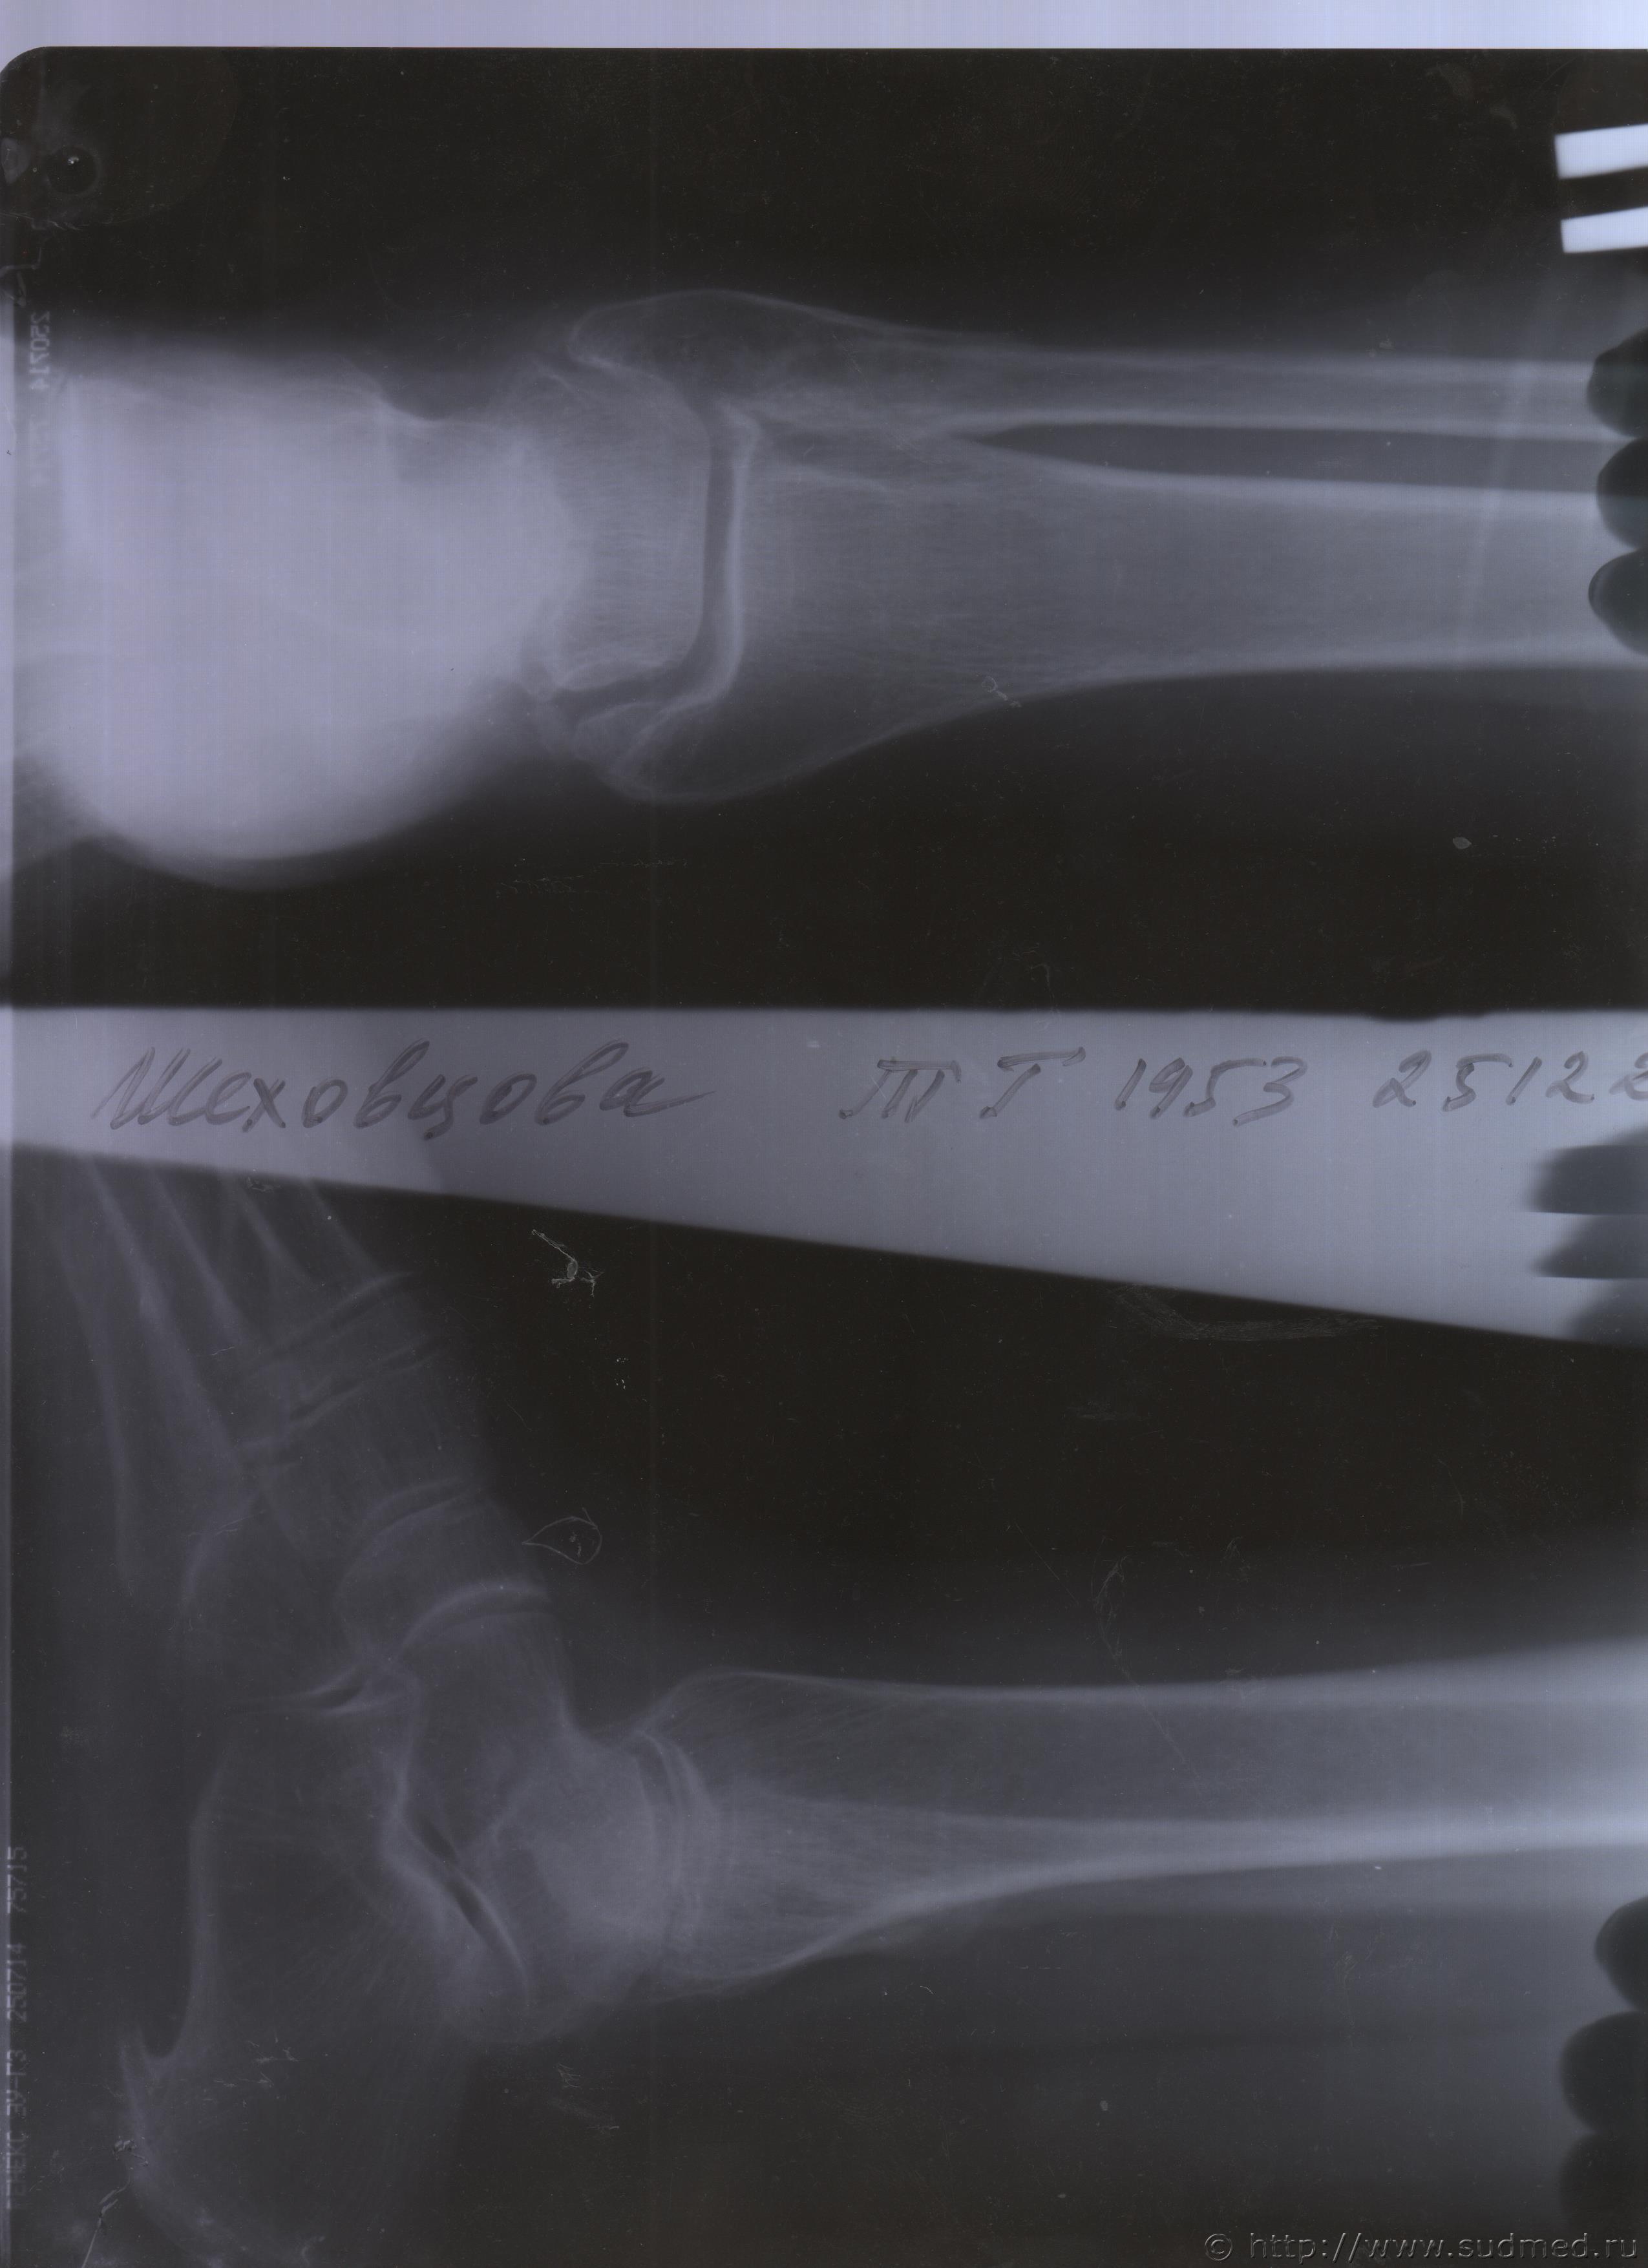

06.07.2015 г. при обращении в горбольницу мне выдали не описанный снимок( все рентгенологи были в отпуске) и справку № 4379 от 06.07.15 г. где диагноз: закрытый 2-х лодыжечный перелом правой голени без смещения. Копию справки прилагаю

За все 12 месяцев, что была на больничном, 8 раз делали снимки травмированной ноги и все заключения именно : «закрытый 2-х лодыжечный перелом правой голени без смещения».

После того, как был поставлен диагноз : «компрессионный перелом L2 позвонка поясничного отдела позвоночника». Амбулаторная мед карта, была украдена из кабинета врача травматолога. При восстановлении мед карты( в марте 2016 г.), врачом травматологом была взята копия справки от 06.07.15 г.из приемного отделения горбольницы. Справка № 4379 ( дубликат), диагноз : «закрытый 2-х лодыжечный перелом правой голени без смещения».

Посмотрите, это снимки за 12 месяцев.

Уважаемая Татьяна! По представленным Вами снимкам ничего сказать нельзя: нет маркировки даты каждого снимка (поэтому, невозможно их сравнивать друг с другом и соотносить с датой травмы), исследование непосредственно пленок гораздо более информативно, чем анализ представленных изображений (детали костной структуры в зоне перелома практически не видны).

Рекомендую проконсультировать все эти снимки у высококвалифицированного рентгенолога. Далее - по ситуации, т.е. в зависимости от его мнения. В любом случае, есть формальные основания для назначения дополнительной экспертизы, т.к., судя по представленному Вами фрагменту заключения эксперта, на экспертизу не были предоставлены все мед.документы с данными о лечении предъявляемой травмы (Вы пишете, что рентгенограммы делались на протяжении 12 месяцев, полагаю, что Вы и врачами наблюдались в течение этого срока, т.е. велась мед.карта).